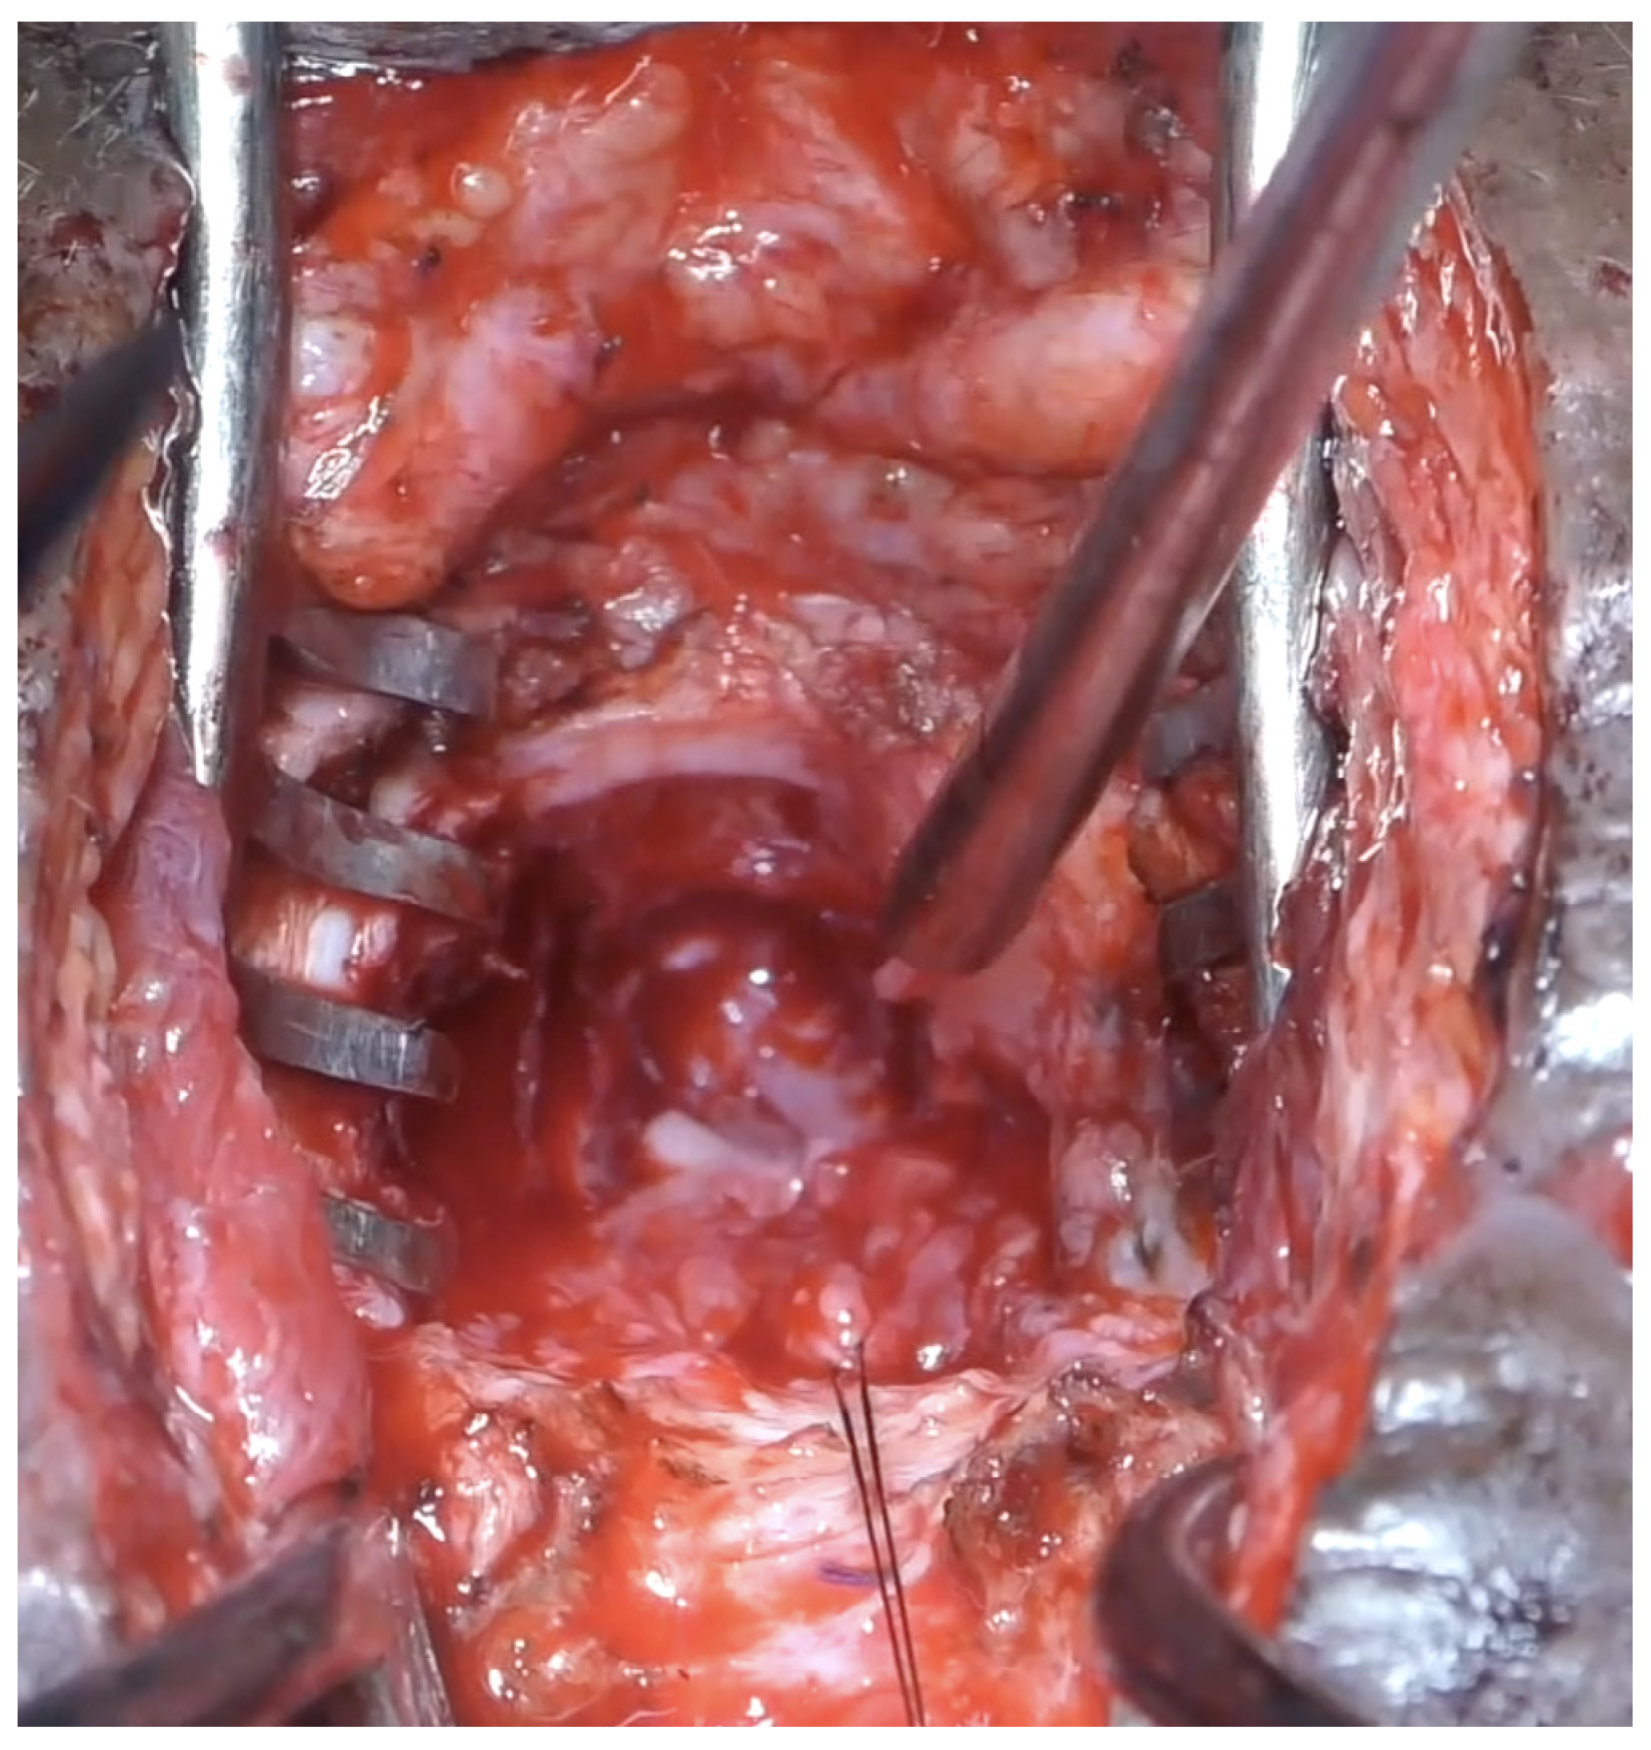

Surgical repair was performed through a lower abdominal incision. The extraperitoneal space was entered and the bladder was released from its anterior attachments. A posterior and superior pubectomy was then performed (Figure 5). Scar tissue at the site of injury was excised. The urethra distal to the injury was incised over a dilator passed through the urethra from the meatus (Figure 6).

Figure 5.

Abdominal approach with posterior and superior pubectomy.

Figure 6.

A 12 Fr mini nephroscope was passed through the suprapubic catheter site to guide the incision of the bladder. The anastomosis between the bladder neck and the urethra was performed with six 5-0 polydiaxone sutures. The posterior sutures were tied down (Figure 7) before passing a 14Fr silicon catheter across the anastomosis and tying down the anterior sutures. The omentum was mobilized and transposed onto the anastomosis. A drain was not usually required.

Figure 7.

Anastomosis.